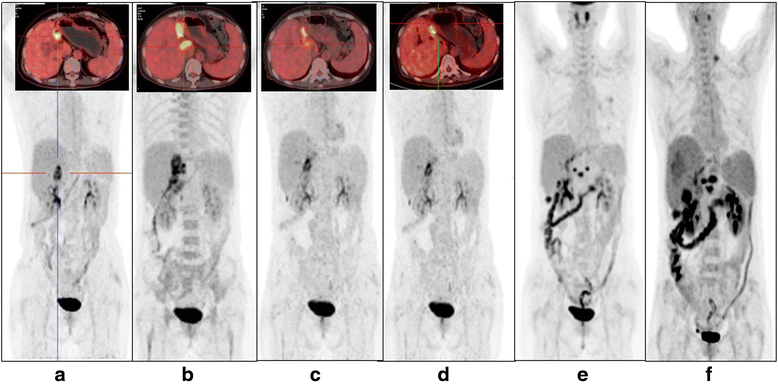

Case presentation: In this case, a 52-year-old female who was diagnosed as advanced unresectable/metastatic CCA and resistant to the following chemotherapy and radiotherapy was treated with CART cocktail immunotherapy, which was composed of successive infusions of CART cells targeting epidermal growth factor receptor (EGFR) and CD133, respectively. The patient finally achieved an 8. 5-month partial response (PR) from the CART-EGFR therapy and a 4. 5-month-lasting PR from the CART133 treatment. The CART-EGFR cells induced acute infusion-related toxicities such as mild chills, fever, fatigue, vomiting and muscle soreness, and a 9-day duration of delayed lower fever, accompanied by escalation of IL-6 and C reactive protein (CRP), acute increase of glutamic-pyruvic transaminase and glutamic-oxalacetic transaminase, and grade 2 lichen striatus-like skin pathological changes. The CART133 cells induced an intermittent upper abdominal dull pain, chills, fever, and rapidly deteriorative grade 3 systemic subcutaneous hemorrhages and congestive rashes together with serum cytokine release, which needed emergent medical intervention including intravenous methylprednisolone V体育安卓版. .